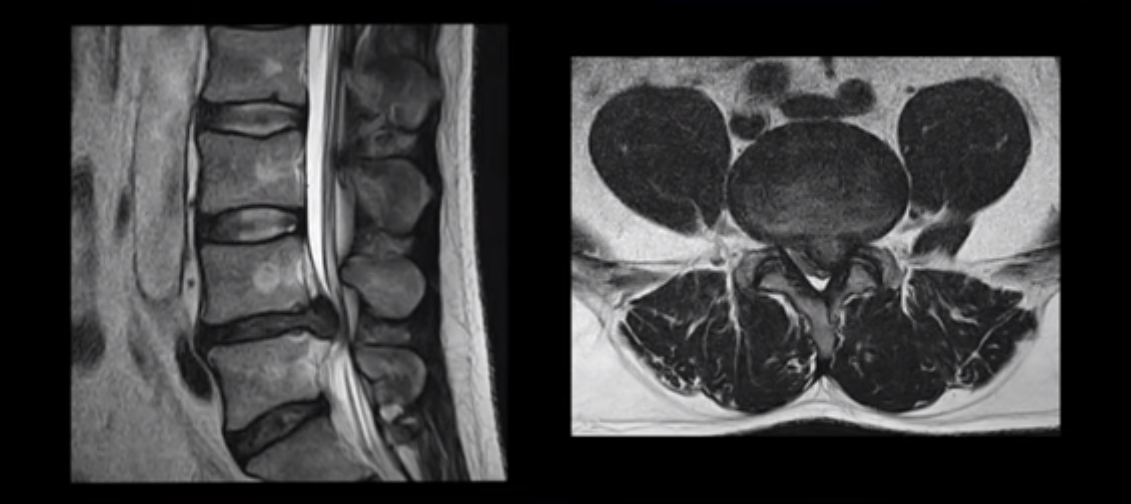

허리디스크 보존치료 좀 경험했다는 환자분들이 자기 경험으로 빗대어 방사통은 원래 오래 가는 것이 당연한 것처럼 말하는 경우가 많습니다. 그런데 저희 같은 비수술 척추치료를 전문적으로 10년 이상 수만 명씩 하고 있는 병원의 입장에서 보면 매우 답답하고 안타깝습니다. 그럼 이 4주 얘기가 파열이 심하지 않은 환자 얘기인지 궁금하실 텐데, 전혀 아닙니다. 여기 보는 MRI처럼 이 정도로 파열이 심하고, 심지어는 마비까지 있는 사람들의 이야기입니다. 이런 사람들이 최적화된 조건 하에서 평균 4주면 방사통이 가라앉는 것입니다.